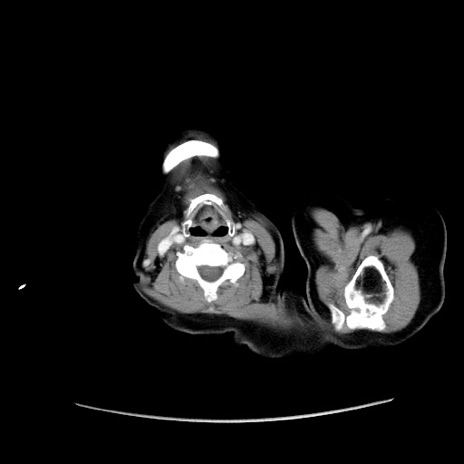

冠状断像

症例19(横断像)

【症例】80歳代女性

【主訴】下腹部痛

【現病歴】約8時間前より下腹部痛の出現あり、救急外来受診。

【既往歴】両側付属器切除

【身体所見】意識清明、下腹部正中に手術痕あり、その部位に一致して圧痛と反跳痛あり。腸蠕動音は亢進。

【データ】WBC 9300、CRP 0.15